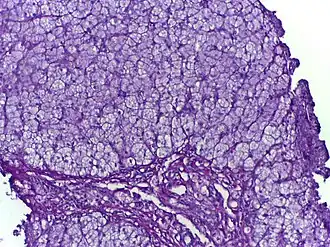

- métabolisme du glycogène ou glycogénose. Comme le glycogène est le carburant musculaire, beaucoup de ces maladies se manifestent comme des maladies musculaires ou myopathies. Les myopathies en rapport avec une anomalie du métabolisme du glycogène font partie des myopathies métaboliques ;

Glycogénoses